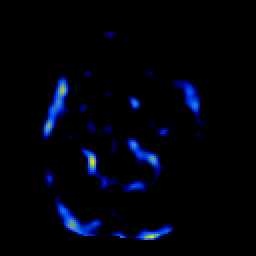

SPECT TL Study #1 -- Slice #26

[Home][Help][Clinical][Tour 1][Tour 2][Tour 3] Slice 26